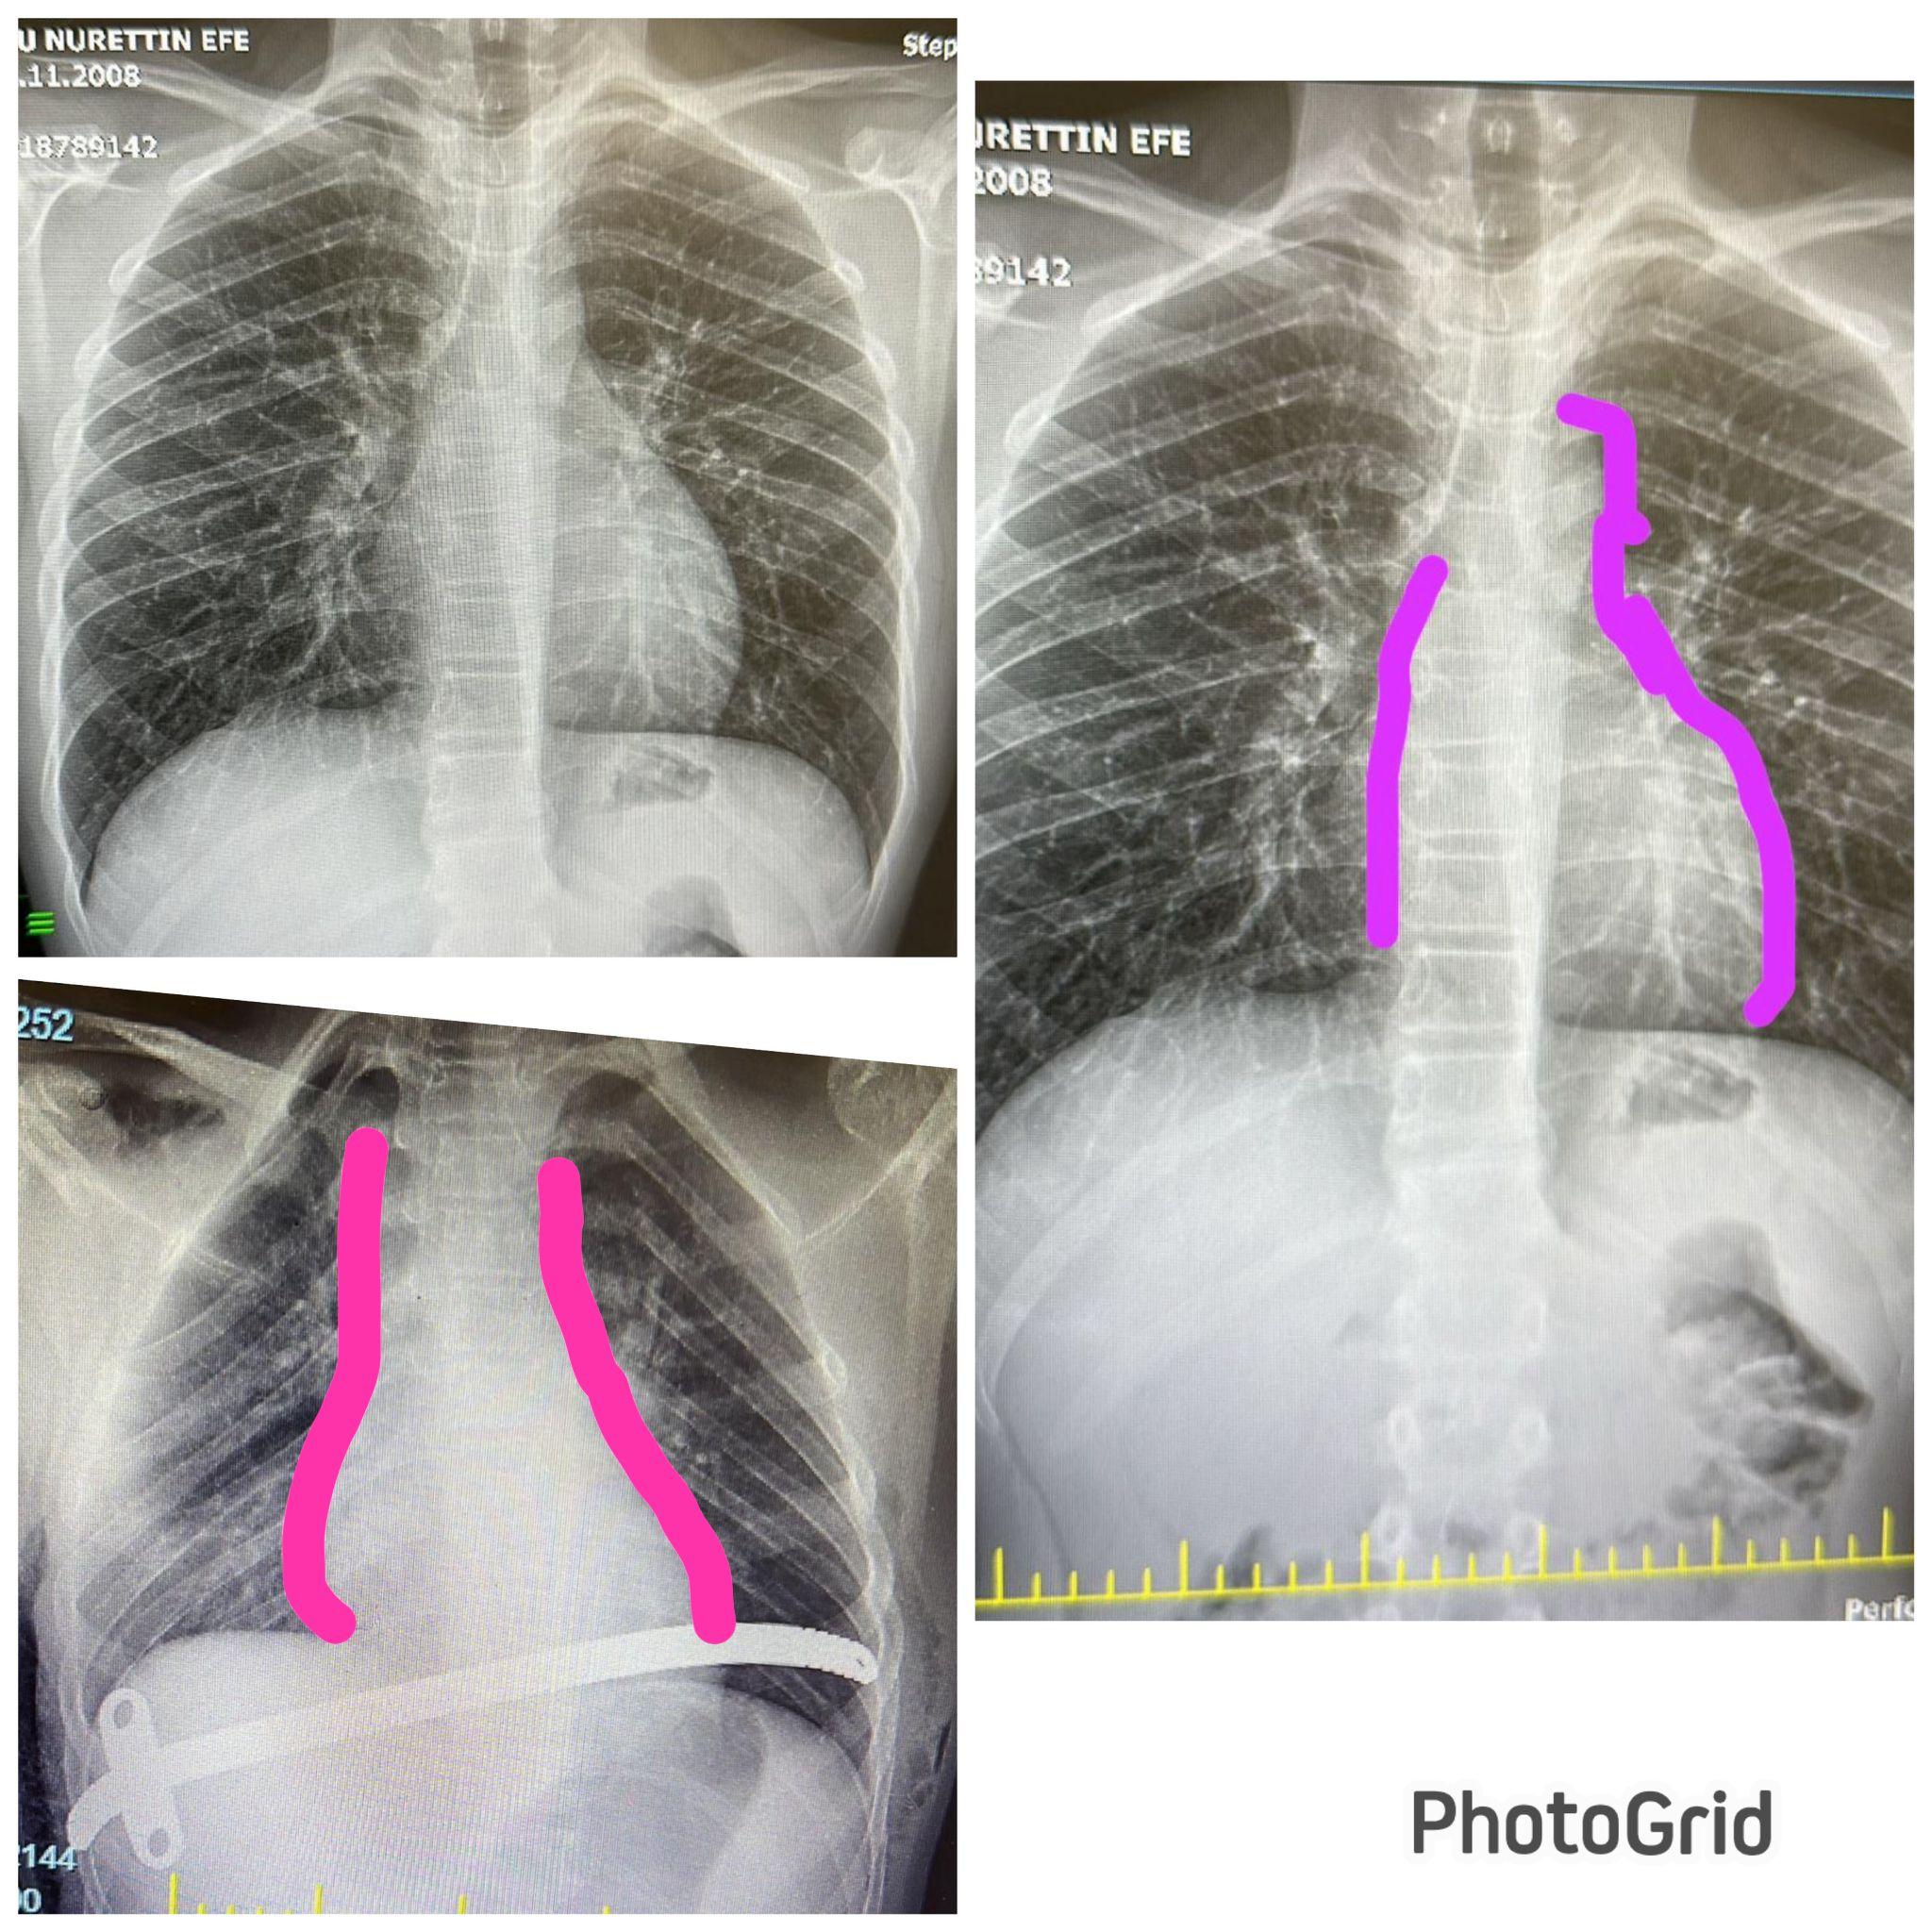

çift barla pektus düzeltilmesi